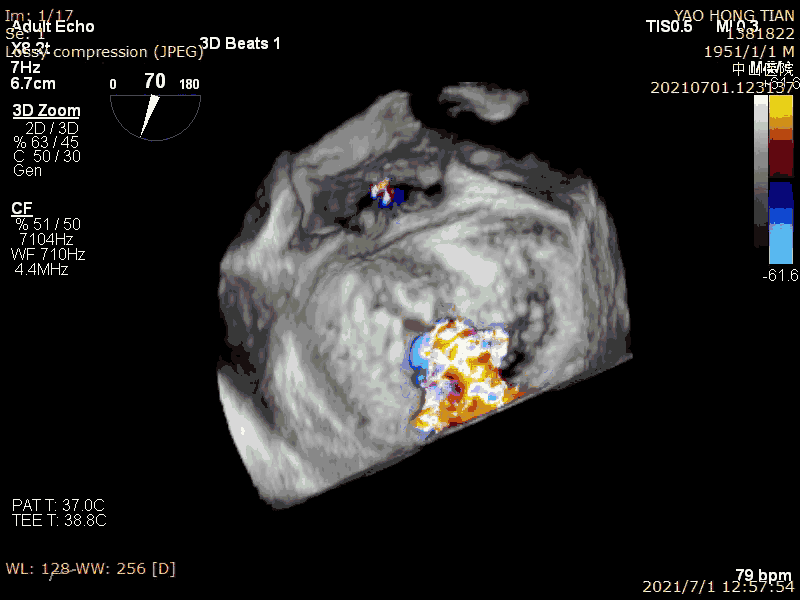

患者,男,70岁。术前超声诊断:左心室射血分数 LVEF 58%,左心室舒张末内径LVDD 52mm,左心房内径LAD 57mm,PASP 63mmHg,二尖瓣瓣尖错位导致重度二尖瓣反流,VC 6*13mm,反流面积19.8cm²(图1-2)。

术前大量反流(VC 6*13mm)

瓣尖错位导致A2P2大量反流